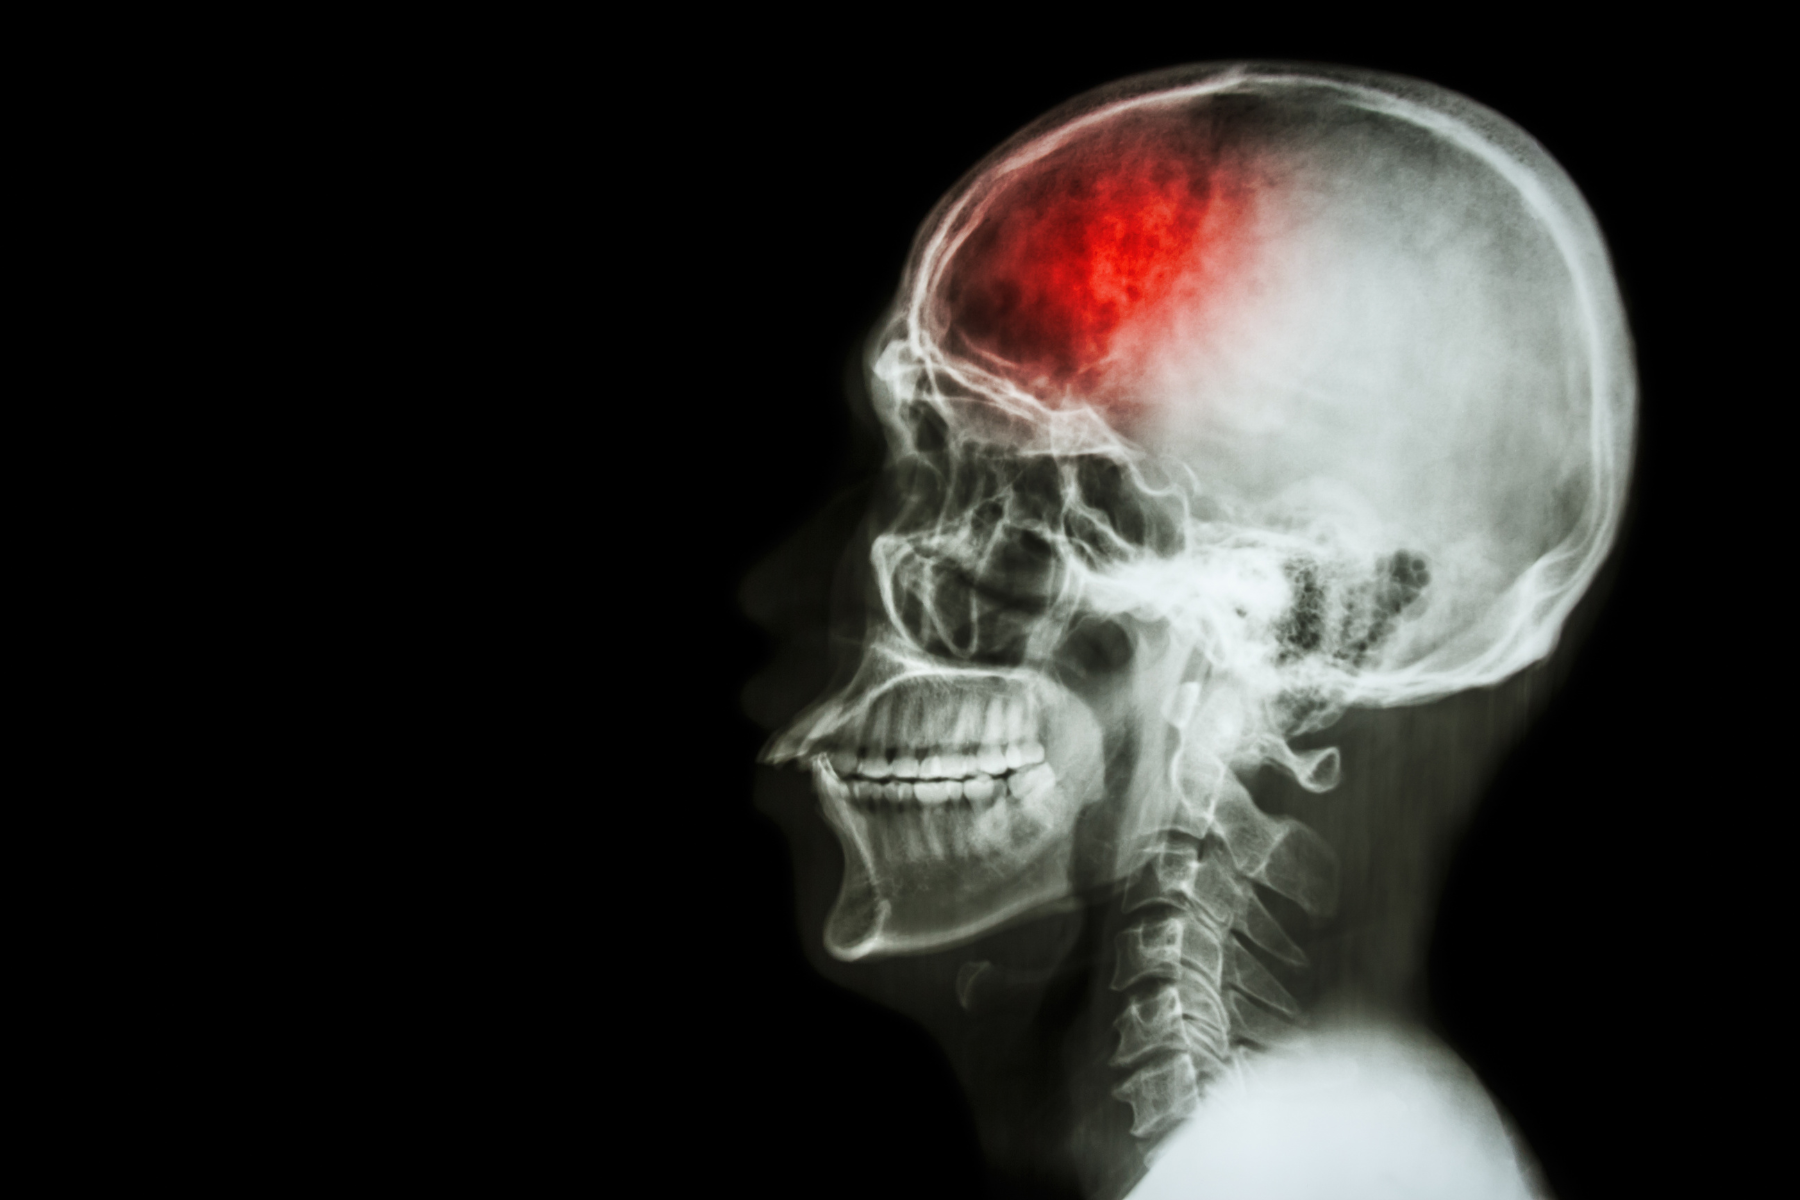

Всесвітній день боротьби з інсультом

29 жовтня – ми відзначаємо Всесвітній день боротьби з інсультом (World Stroke Day). Інсульт є одним з найпоширеніших захворювань у всьому світі, зокрема, у нашій країні. Цей стан займає 2 місце серед найтяжчих захворювань України. Що таке інсульт і чому ми приділяємо йому таку увагу? Інсульт – гостре порушення мозкового кровообігу, через раптове припинення кровопостачання мозку. Наслідком захворювання може бути інвалідність, яка змінює якість життя та праці людини. Це дуже актуальна проблема у нашій країні і вона займає одне з найважливіших місць у медицині.